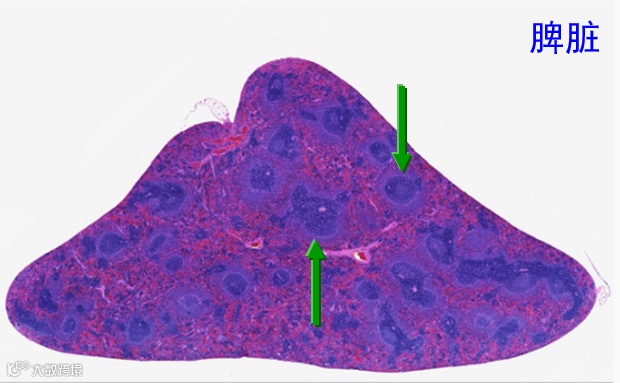

慢性应激变化可导致淋巴细胞耗尽和淋巴组织萎缩,应正确辨别细胞正常、细胞退化、组织萎缩的差异。

大鼠脾-正常的淋巴细胞鞘

大鼠脾-淋巴细胞耗尽/组织萎缩